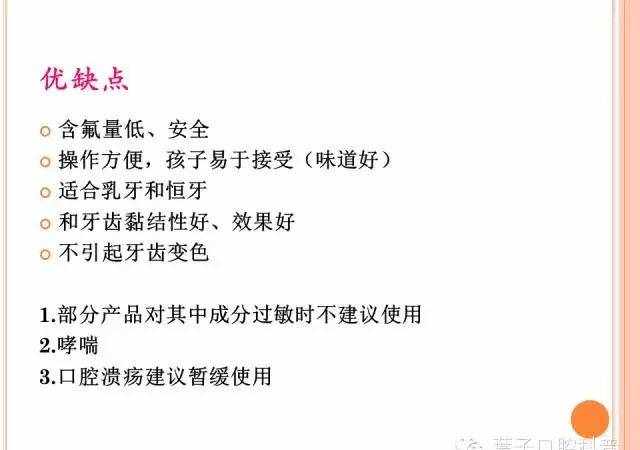

护牙素

为了帮助修护牙齿表面脱矿的釉质,像护牙素这类产品便兴起了。护牙素可促进钙和磷酸盐对釉质的修复与坚固,从而修复出现表面白斑的牙齿,从微观上填补釉质表面细小的坑洞与裂纹。

护牙素优势

修复或者防止早期龋齿 减少敏感度护牙素类型(以日本G牌护牙素为例)

G牌无氟护牙素 此类护牙素的特有的成分是:牛奶中的酪蛋白所提取的Recaladent(CCP-ACP) G牌升级版—含氟护牙素 此类护牙素的优点在于将氟化物混入其中,促进钙和磷酸盐对釉质修复的同时也传送了大量的氟化物。护牙素如何使用

使用护牙素很简单,就是用一根手指或者一个软刷轻轻地在牙齿上(用护牙素)摩擦。

√ G牌护牙素升级版推荐六岁以上的患者使用,理由是它的氟化物含量(高)。但是,也有一种不含氟化物的配方适用于年幼的患者。

× 对牛奶或苯甲酸防腐剂过敏的患者不适合用G牌护牙素。

G牌护牙素的pH值为中性,不会促使牙齿受到酸侵蚀,反而,它会使牙齿更有能力去抵抗腐烂,并且能够通过预防或改善白斑而使牙齿更美观。

护牙素何时使用

在睡前清理完牙齿再使用护牙素是最佳的。因为睡着时候口水流动得少,会使护牙素的益处发挥到最大化。

使用两到三分钟,然后将多余的分量吐出,只留下薄薄的一层在牙齿上。如果吞下(少量)护牙素是安全的。